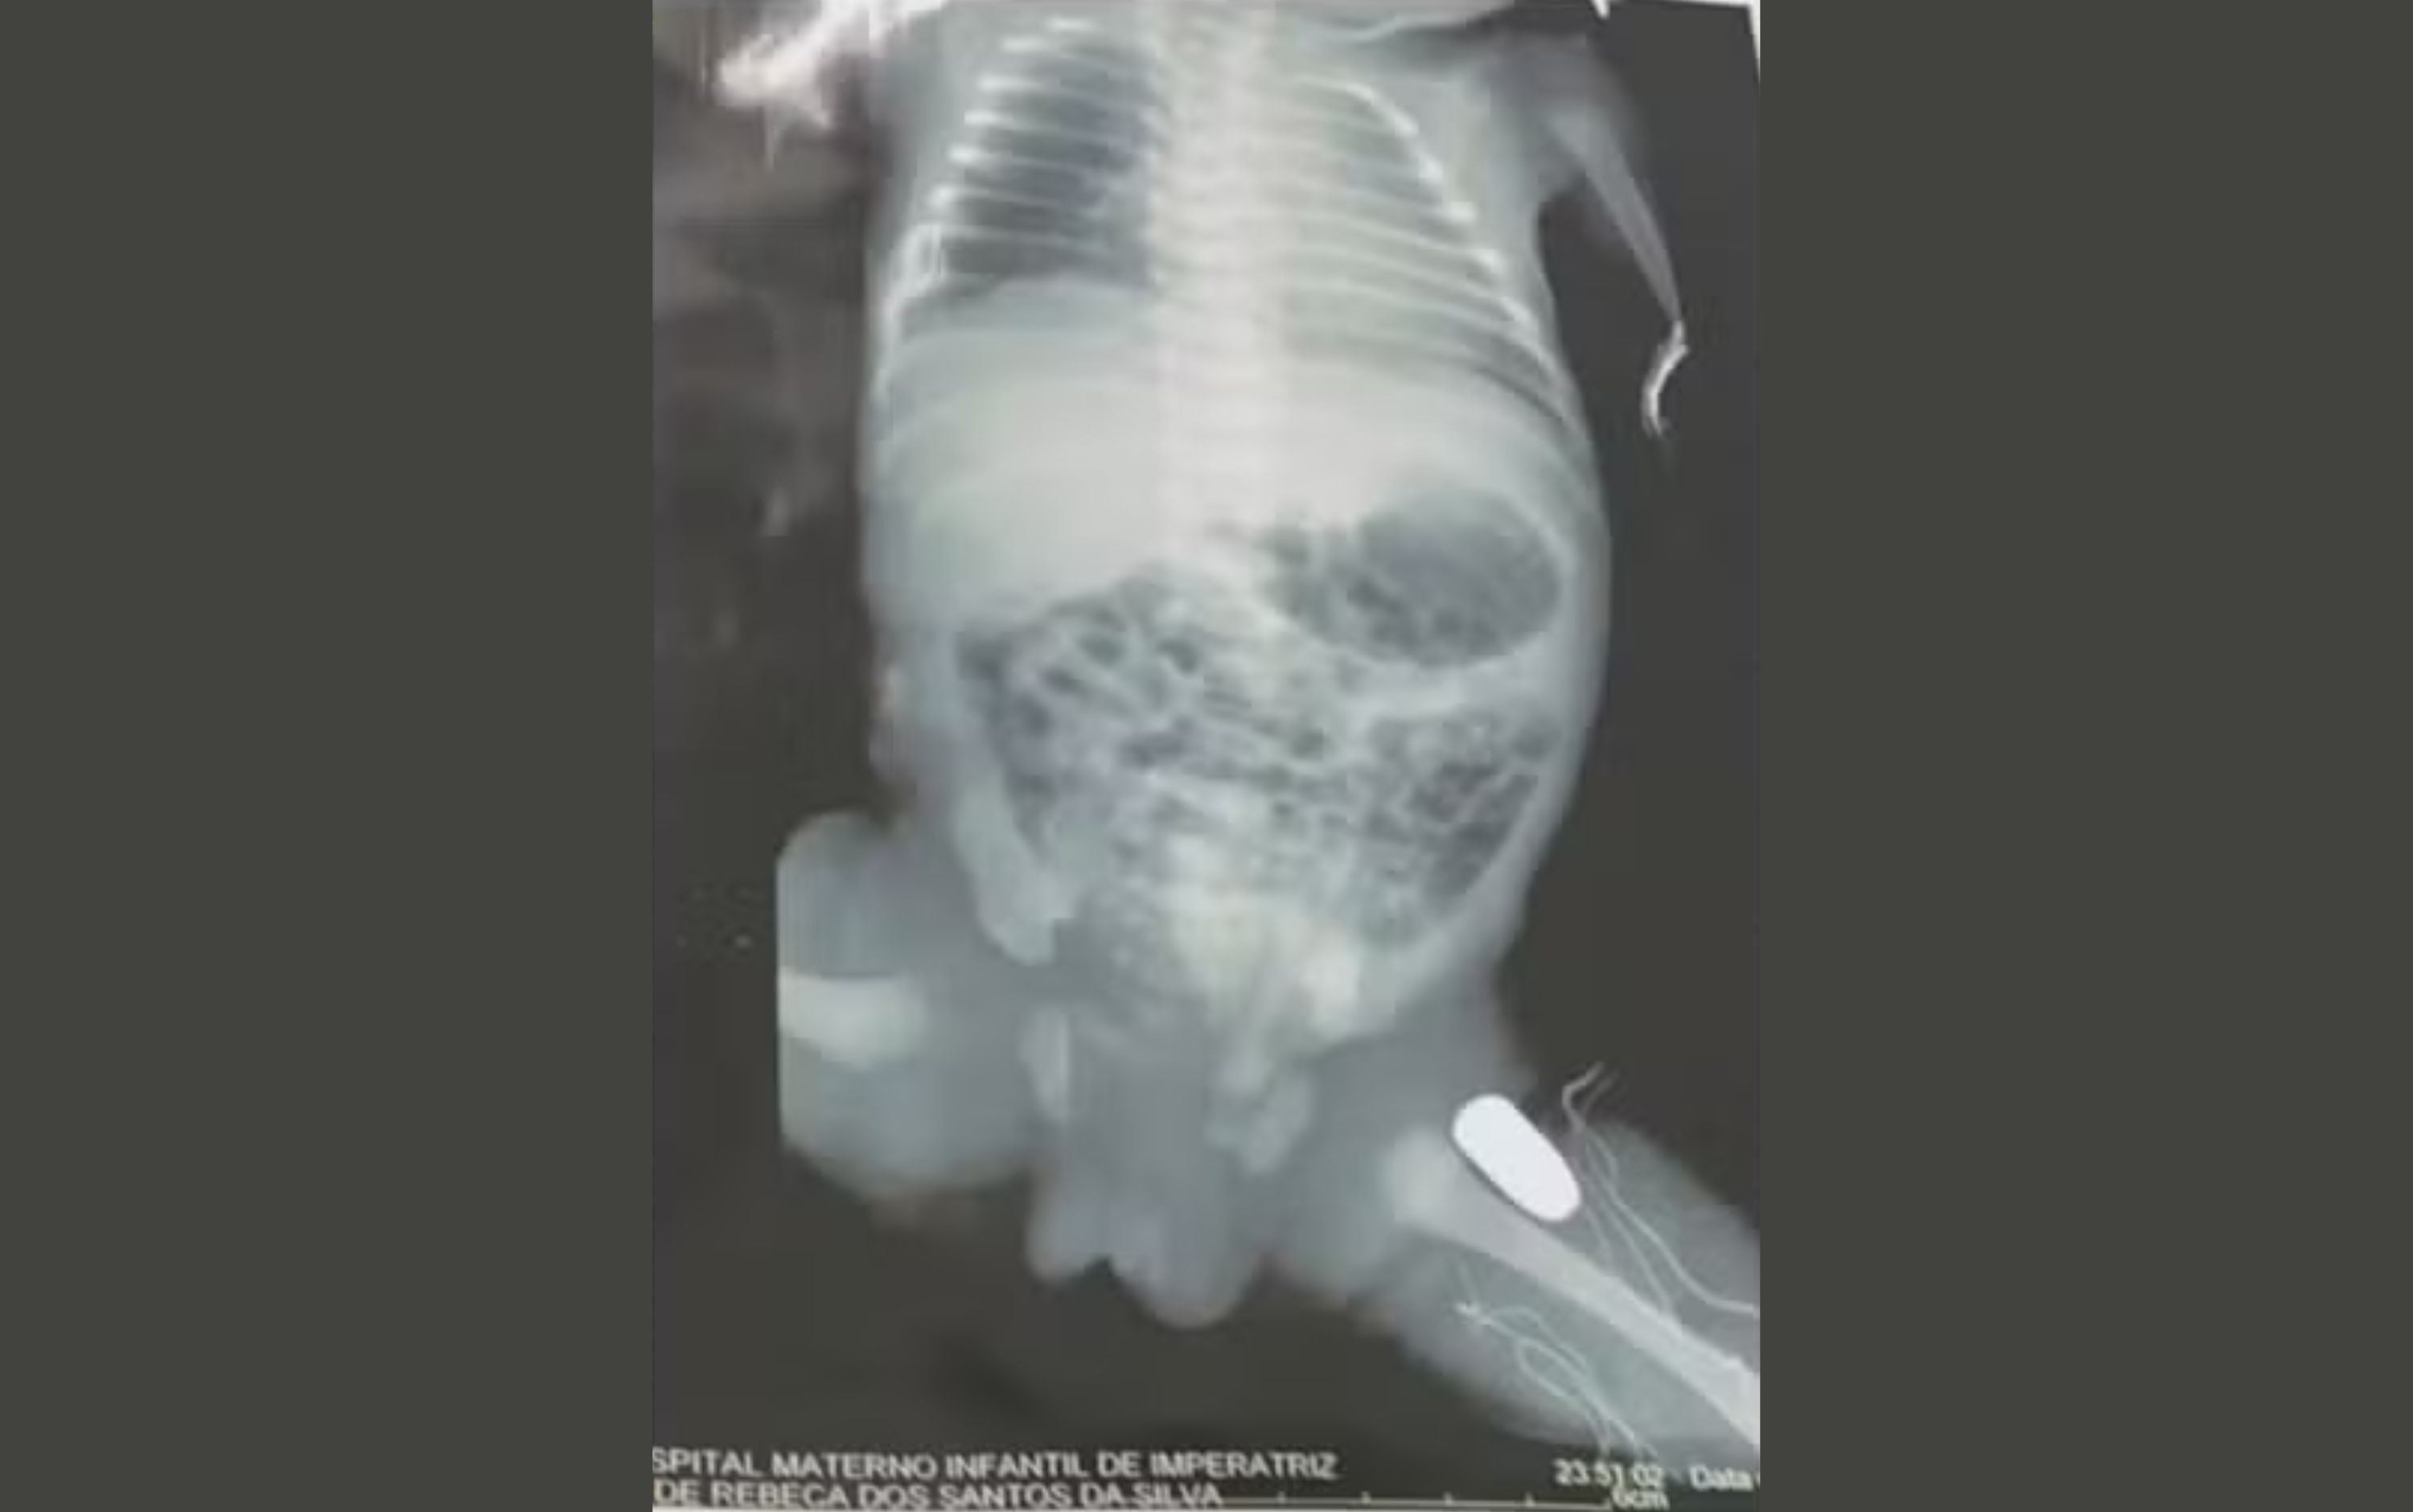

Uma adolescente de 15 anos, grávida de nove meses, levou um tiro na barriga durante uma tentativa de assalto, no domingo (16), ena cidade de Imperatriz, no Maranhão. A bala ficou alojada na perna do bebê.

O bebê ficou com a bala alojada em uma das pernas e deve passar por uma cirurgia, ainda hoje, para remover o projétil.